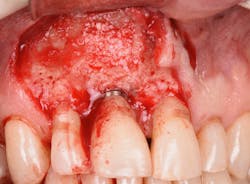

Figure 14: After osseous shaping and recontouring was done using the Er:YAG laser in contact mode (20 pps/80 mJ). All bony ledges and crestal bone were removed on teeth Nos. 9–11.